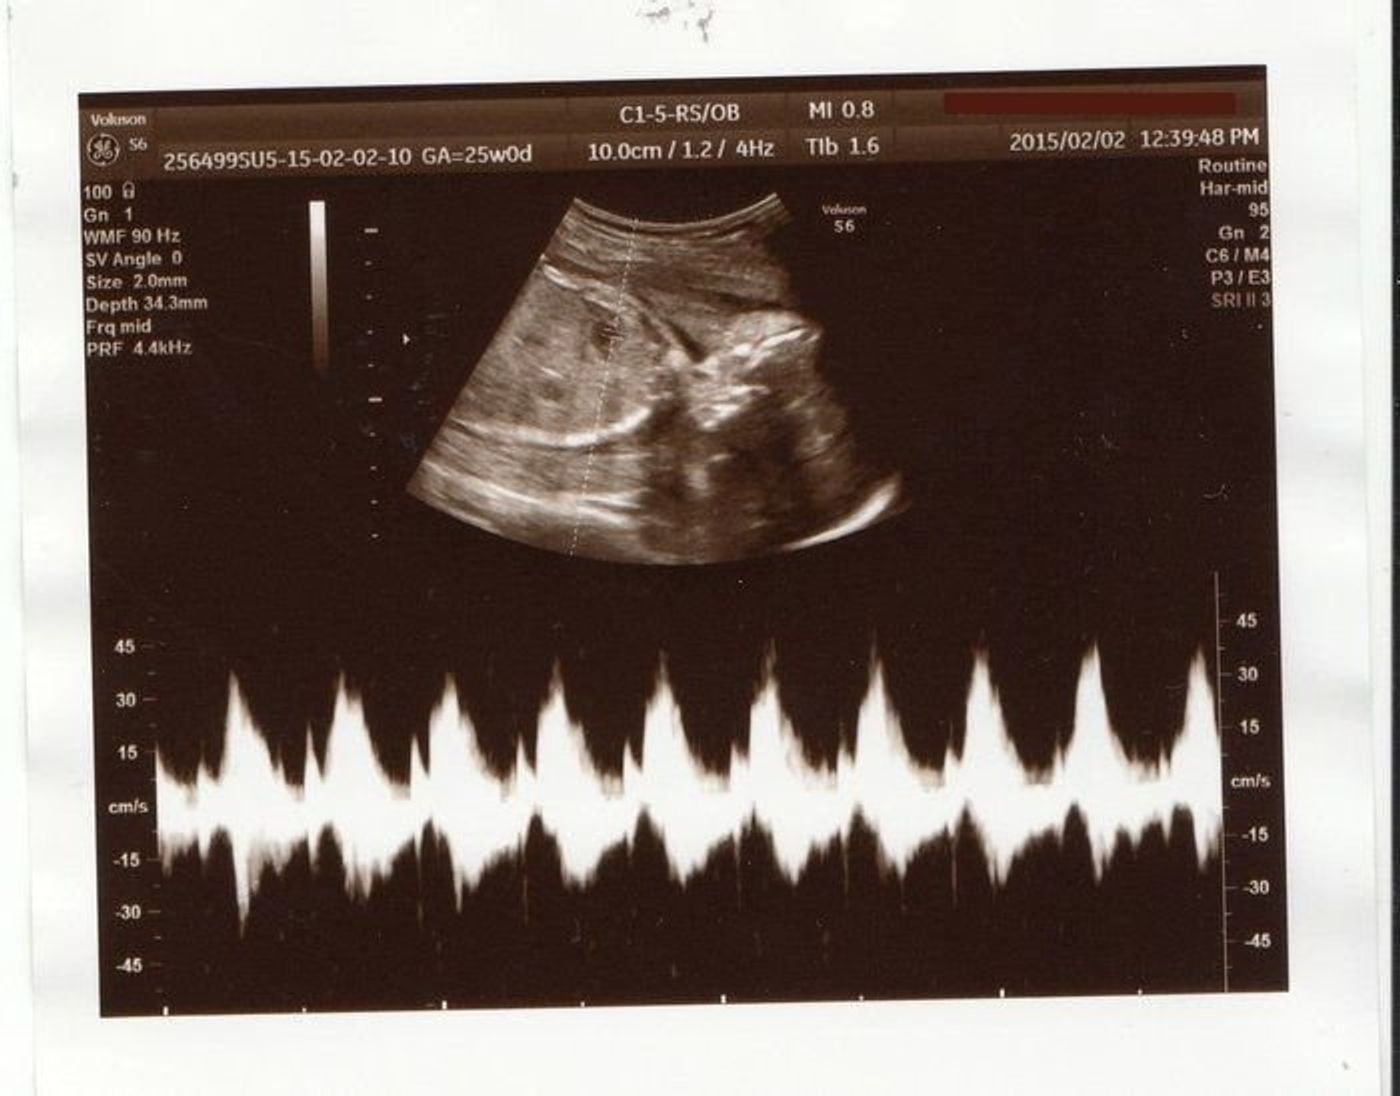

25週3日 エコー

妊娠25週3日 25w3d の超音波 エコー 写真